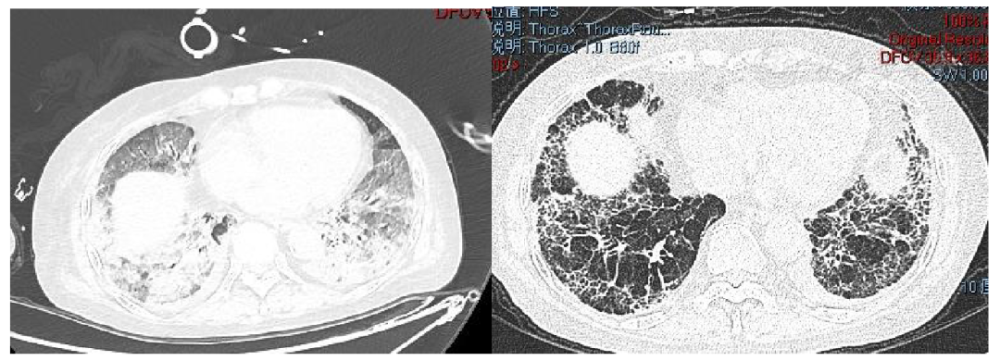

肺纖維化高發(fā)

《Nature Medicine》2021年發(fā)表了“Post-acute COVID-19 syndrome”,研究指出呼吸困難在60-100天的隨訪期內(nèi)的發(fā)生率為42%-66%,有6.6%的患者因持續(xù)低氧血癥需要補(bǔ)充氧氣。患者出院后3個(gè)月評(píng)估發(fā)現(xiàn)約25%的輕度至中度病例存在纖維化,在重癥病例居多的隊(duì)列中,約65%的康復(fù)者存在肺纖維化。